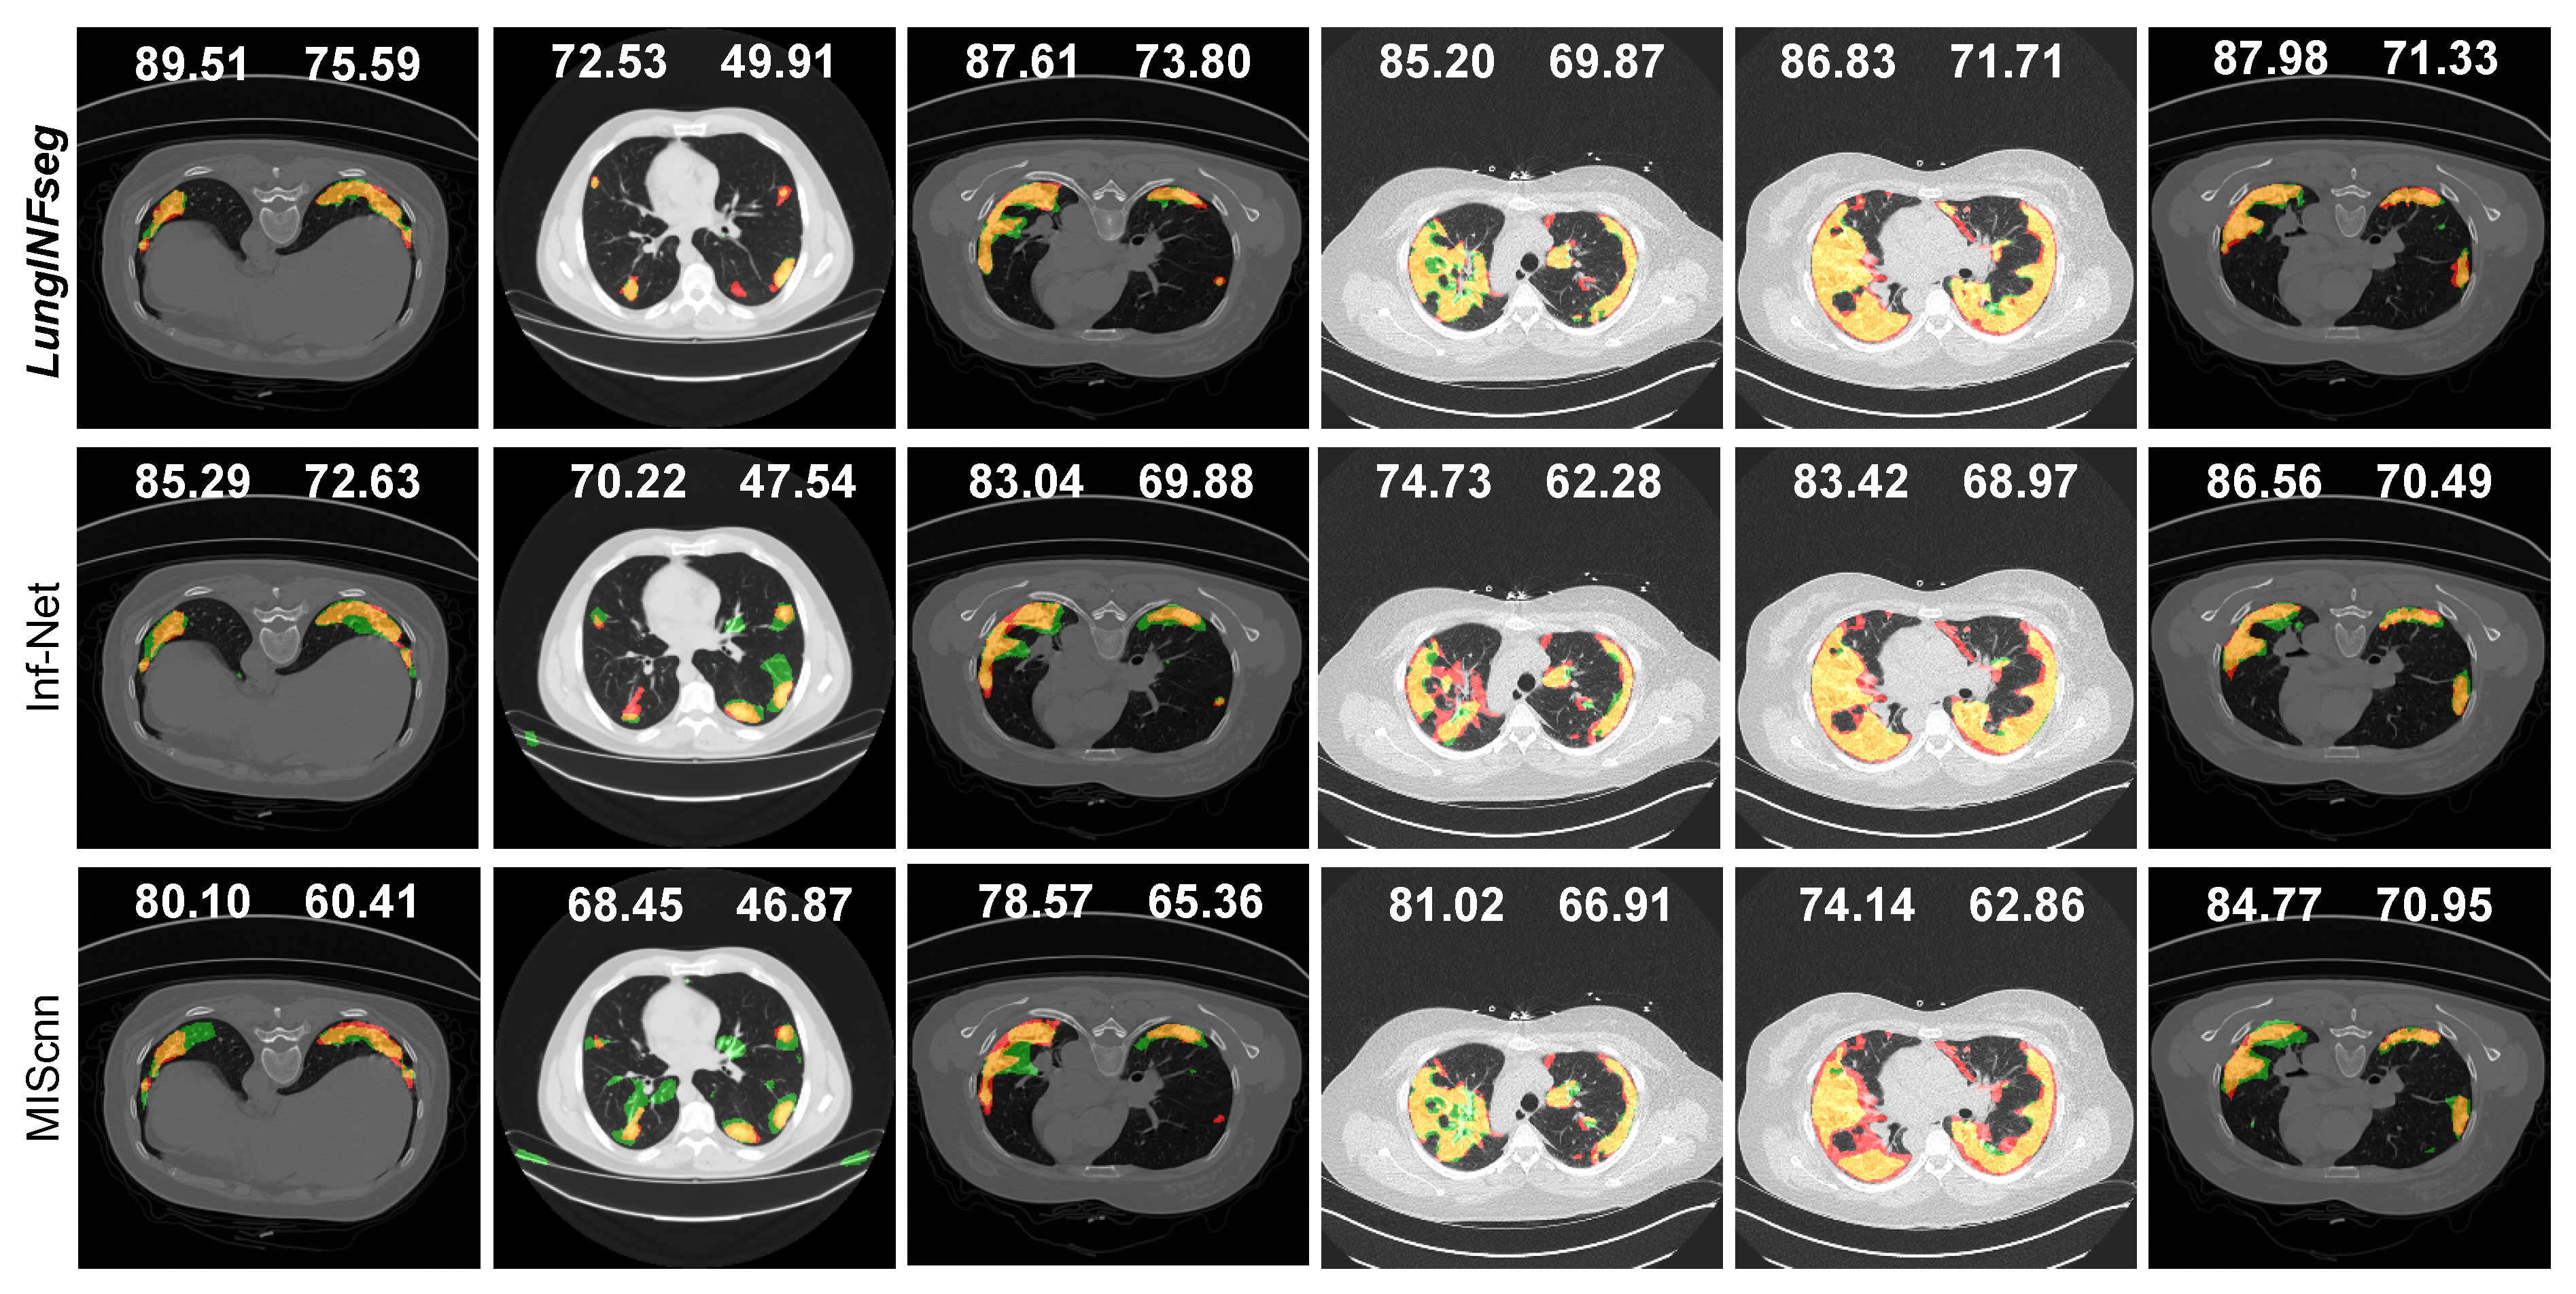

3.4. Comparisons with the State-of-the-Art